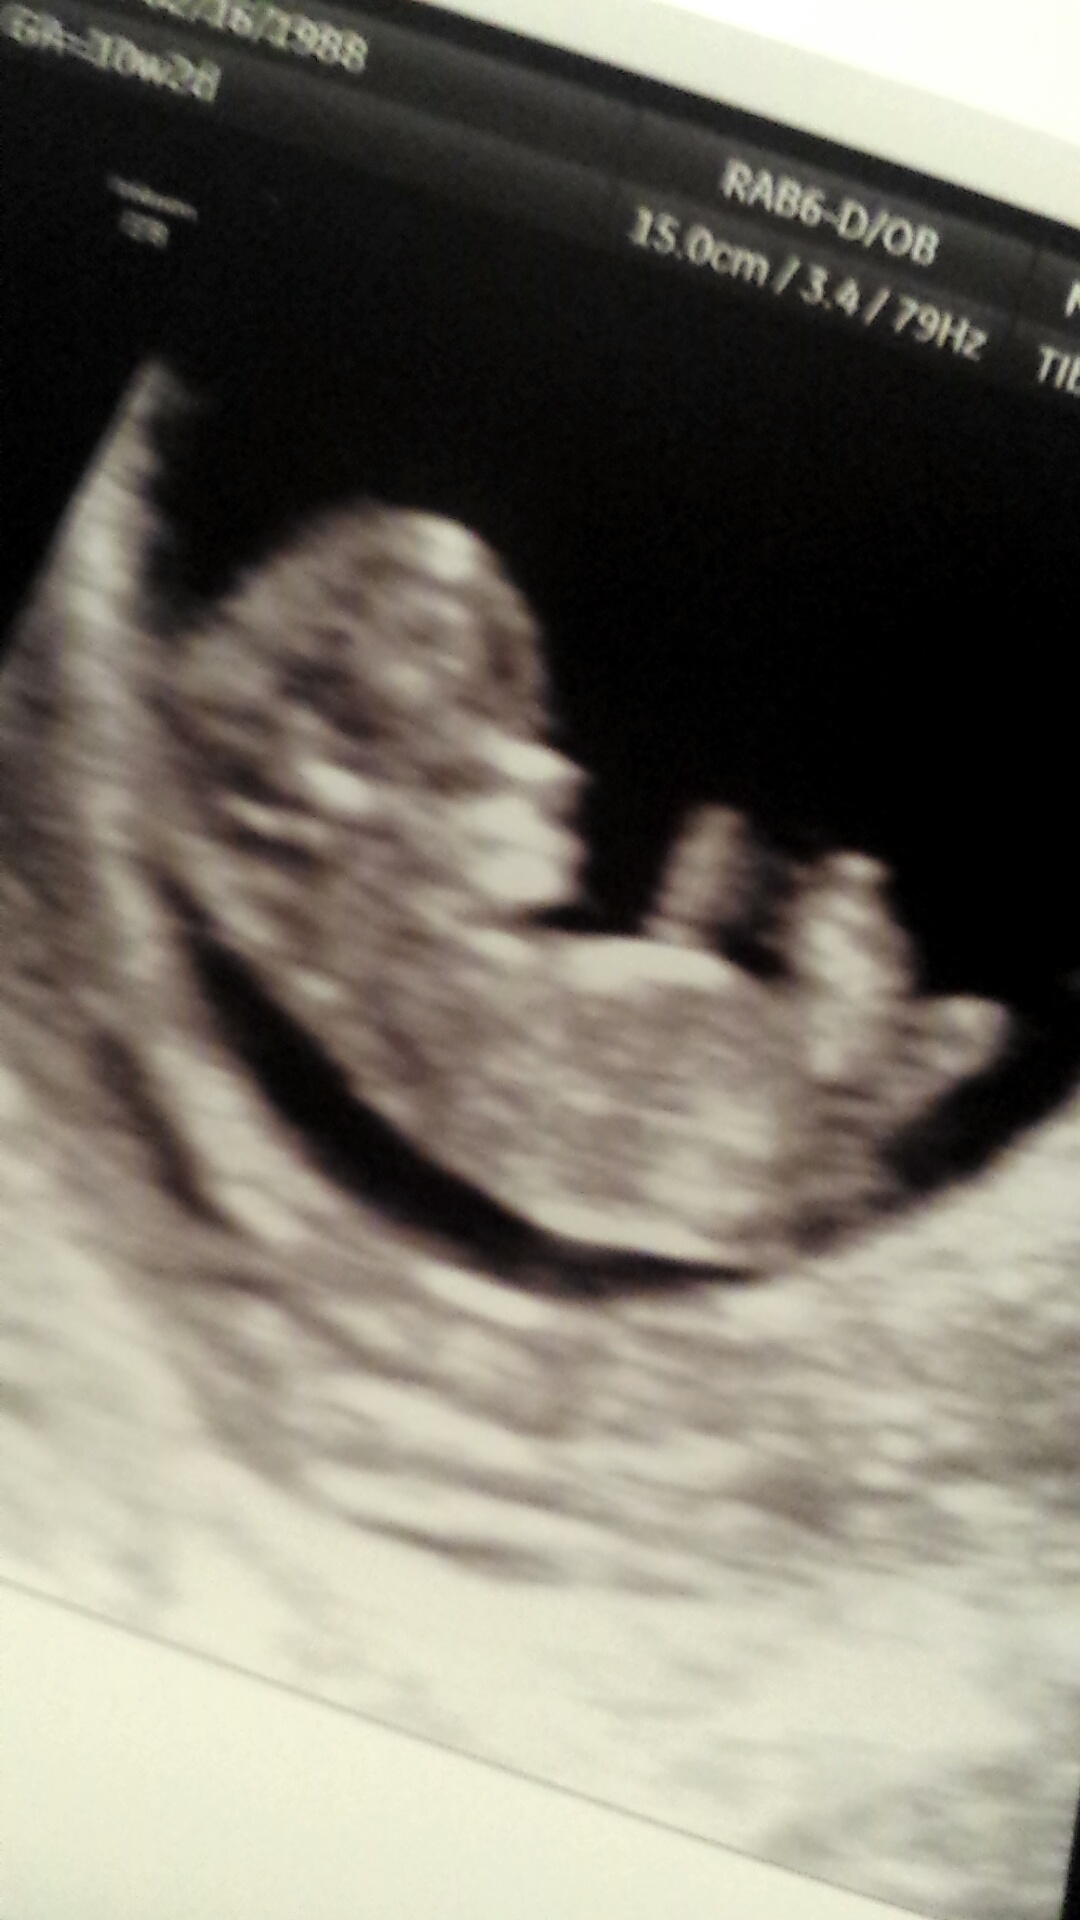

Today was my first ultrasound! I feel so relieved now that everything went well. I'm measuring as I should be. I'm 10w1d. The baby's heart beat was 163! I'm so in love! I can't stop looking at my pictures. I also got to see 3D and it was amazing. Feels so much more real now! I'll have to wait I guess to post my pic